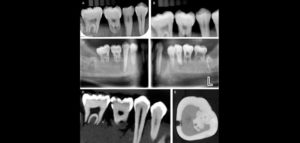

Se sabe que la tomografía computarizada de haz cónico (CBCT) produce exploraciones tridimensionales de la dentición, las estructuras duras maxilofaciales y la relación de las